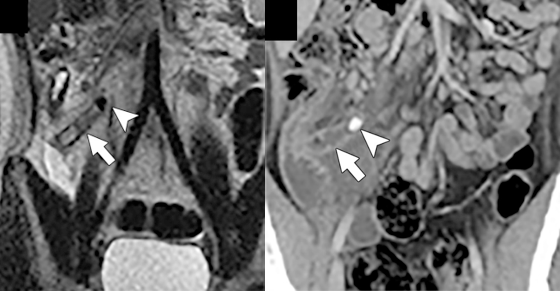

Although CT is the workhorse imaging modality in the emergency department (ED), there are many concerns related to ionizing radiation exposure in populations that are vulnerable due to young age, pregnancy, or exposure to repeated imaging examinations. In patients with nontraumatic acute abdominal symptoms, non-contrast MRI offers similar diagnostic performance to CT. For instance, in a prospectively enrolled cohort of 48 patients with head-to-head comparison of MRI to CT, there was no significant difference in performance for diagnosing acute appendicitis in young adults and adolescents (Fig. 1).